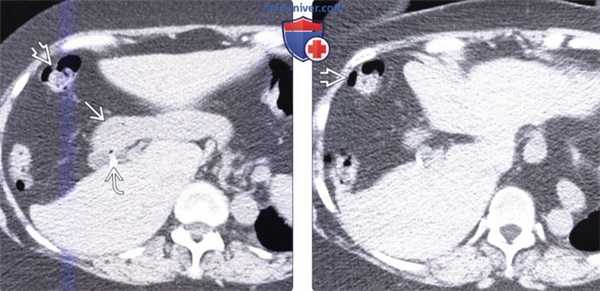

(Слева) На аксиальной КТ с контрастным усилением определяется в значительной степени уменьшенный в размерах медиальный сегмент печени, расположенный между щелью серповидной связки и желчным пузырем. Передние сегменты также уменьшены в размерах.

(Справа) На аксиальной КТ с контрастным усилением в этом же случае визуализируются толстая кишка и жировая клетчатка сальника, заполняющие промежуток между правой и левой долей печени у пациента с врожденной гипоплазией переднего и медиального сегментов.

(Слева) На аксиальной КТ с контрастным усилением определяется гипоплазия переднего и медиального сегментов. Обратите внимание на клипсу после ранее выполненной холецистэктомии (в норме желчный пузырь располагается между долями печени). Также обратите внимание на грыжевое выпячивание желудка и толстой кишки латерально и в краниальную сторону.

(Справа) На более каудальном аксиальном КТ срезе без контрастного усиления у этого же пациента визуализируется свободное пространство, обусловленное врожденной гипоплазией переднего и медиального сегментов печени, заполненное жировой клетчаткой сальника и печеночным изгибом ободочной кишки.